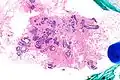

| Very low magnification micrograph of atypical ductal hyperplasia (ADH). The piece with ADH was circled by the pathologist with a marker, as it is so small, and sent for an additional opinion. H&E stain. | |

The name of the entity is descriptive of the lesion; ADH is characterized by cellular proliferation (hyperplasia) within one or two breast ducts and (histomorphologic) architectural abnormalities, i.e. the cells are arranged in an abnormal or atypical way, more so than usual ductal hyperplasia.

ADH, cytologically, architecturally and on a molecular basis, is identical to a low-grade ductal carcinoma in situ (DCIS);[3] however, it has a limited extent, i.e. is present in a very small amount (< 2 mm).